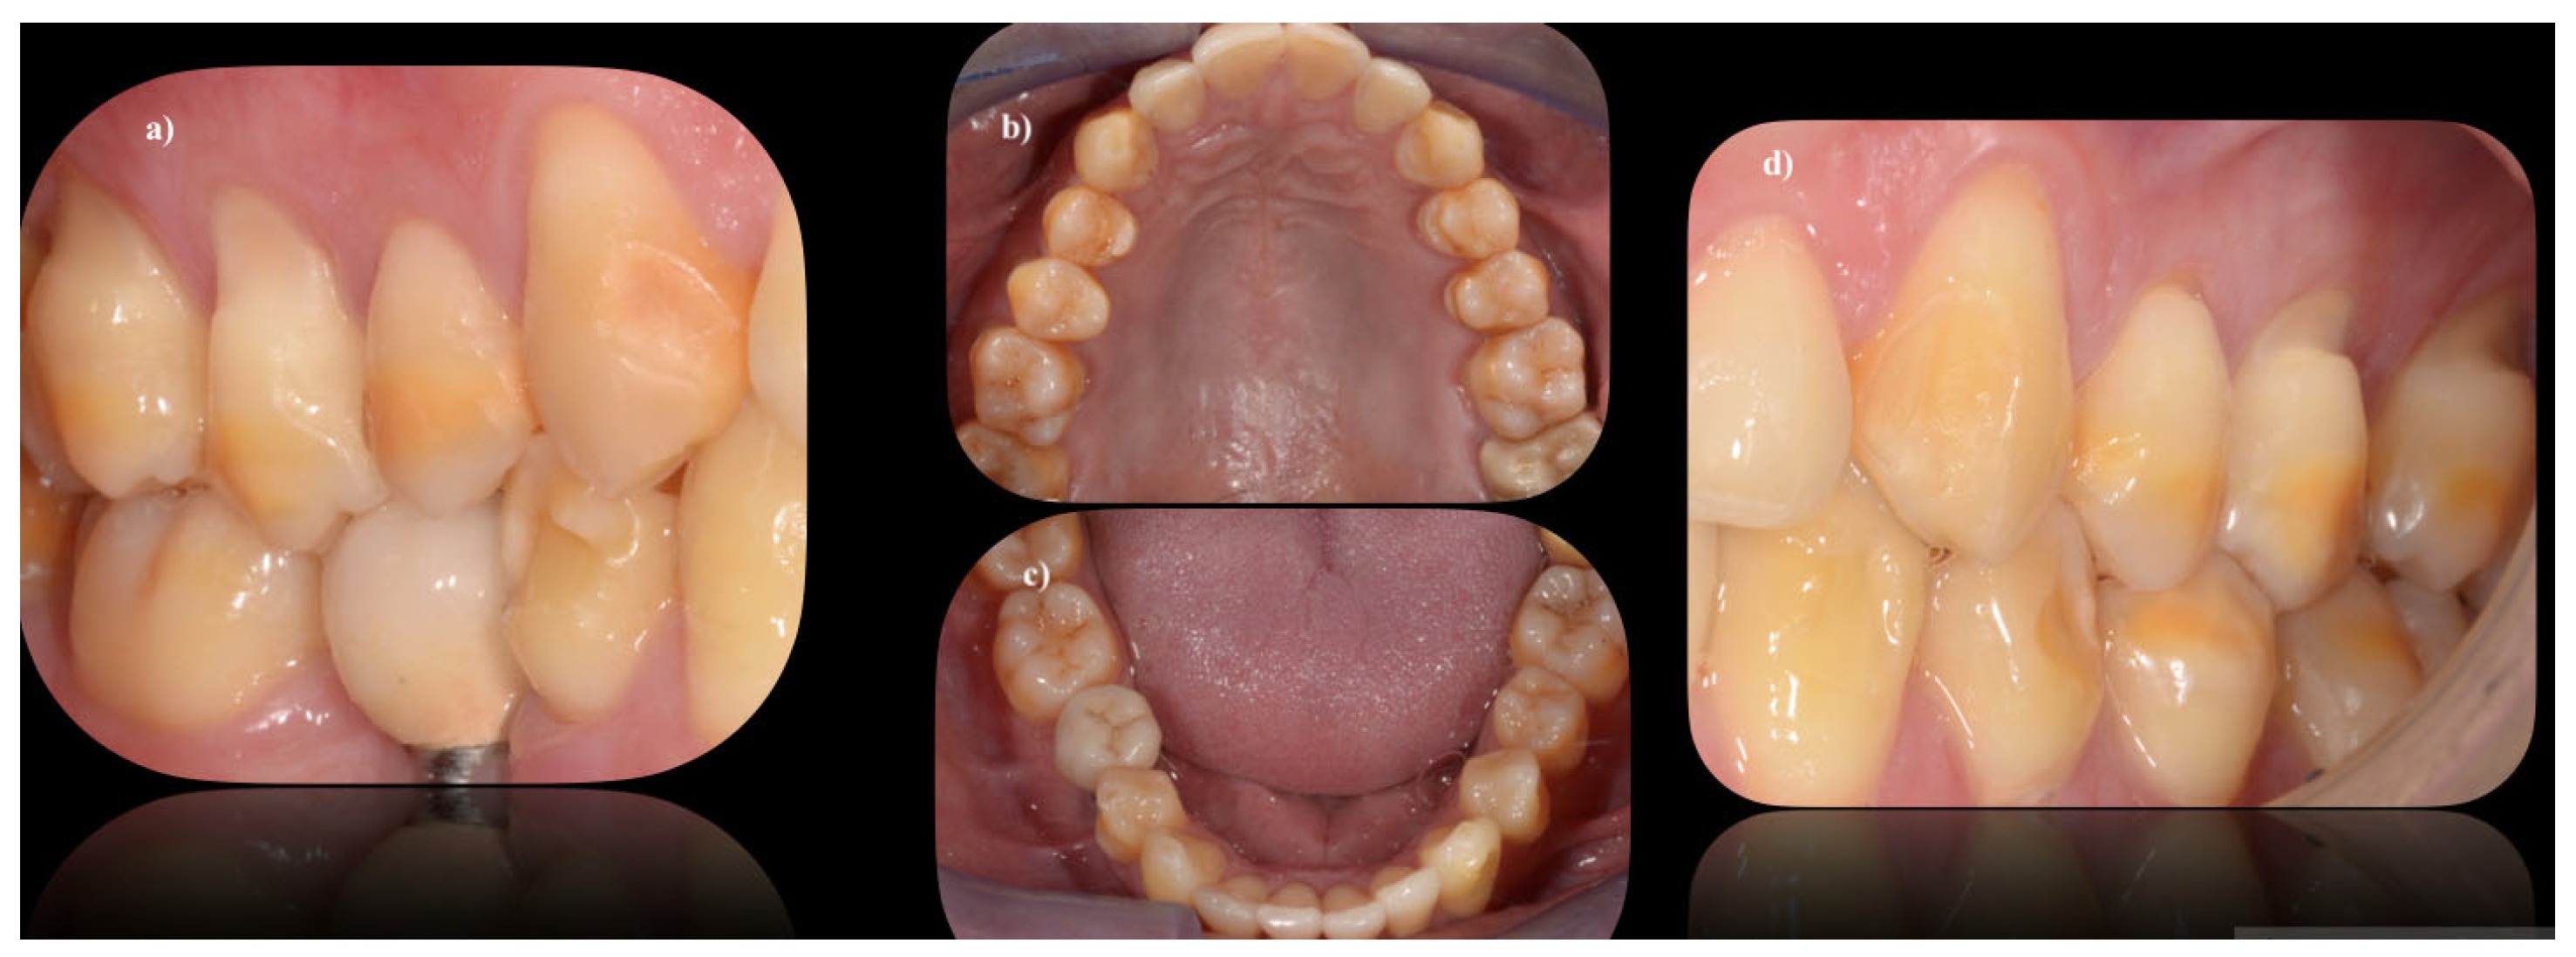

8. Teeth Enamel Wear